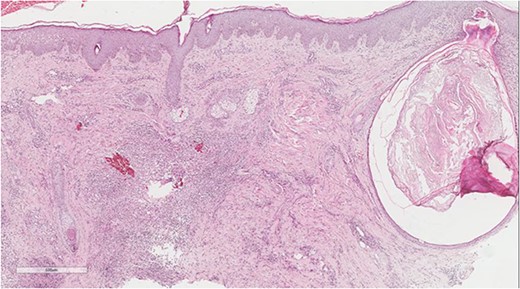

A 5 mm skin punch biopsy was also taken from the neck. Histopathology showed cystically dilated hair follicle with surrounding fibrosis and heavy inflammatory infiltrate and granulation tissue (Fig. 1), the inflammatory infiltrate is composed of lymphocytes, plasma cells, neutrophils and histiocytes (Fig. 2). The overall morphologic picture was suggestive of follicular occlusion syndrome (Fig. 3). A diagnosis of HS was made, and the patient was started on rifampin 600 mg OD and clindamycin 300 mg BID. A lipid panel was ordered as well and showed a triglyceride level of 1.99 mmol/L (0.7–1.7 mmol/L).

Perivascular lymphoplasmacytic infiltrate that is a common finding in HS.